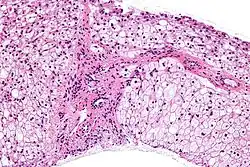

![]() | |

| Glycogen storage disease in hepatocytes | |

| Symptoms | Biopsy shows either abnormal accumulation or deficit of glycogen |